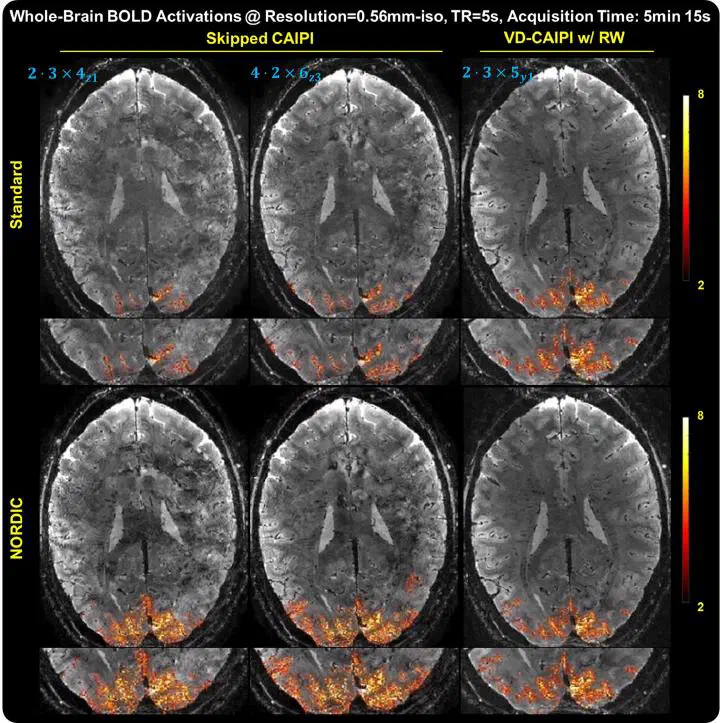

Higher spatial resolution and sensitivity in whole brain functional MRI at 7T using 3D EPI accelerated with variable density CAIPI sampling and temporal random walk